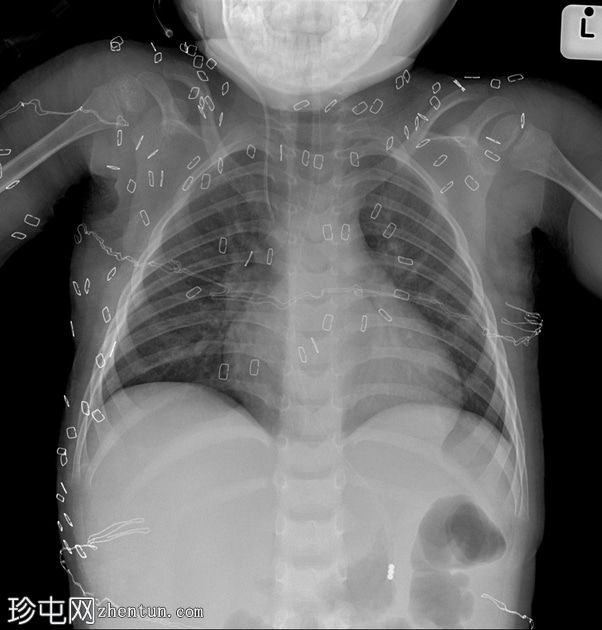

严重三度烧伤。患者曾接受植皮手术,现于重症监护病房进行胸部X线复查。

年龄:3岁

性别:男

部吸气良好。心胸比正常。胃管(NGT)位置良好,右侧颈内静脉(IJV)中心静脉导管置入。

轻度支气管低通气。

胸部可见大量手术钉。胸部中部和腹部中部覆盖有水平方向的医用纱布,可见平行排列的放射线不透光纱布标记。

患者为严重三度烧伤,病因不明。双侧胸部可见大量分散的手术钉,符合植皮病史。可以看到覆盖在膈肌上的水平纱布,这可以从膈肌上下方的线性不透射线标记看出。在重症监护室,各种医疗器械、管路、导管和保温毯很容易让人分心或不知所措。一次只关注一根留置导管、导管、引流管或医疗器械,并从头到尾追踪其位置,有助于提高评估的准确性。